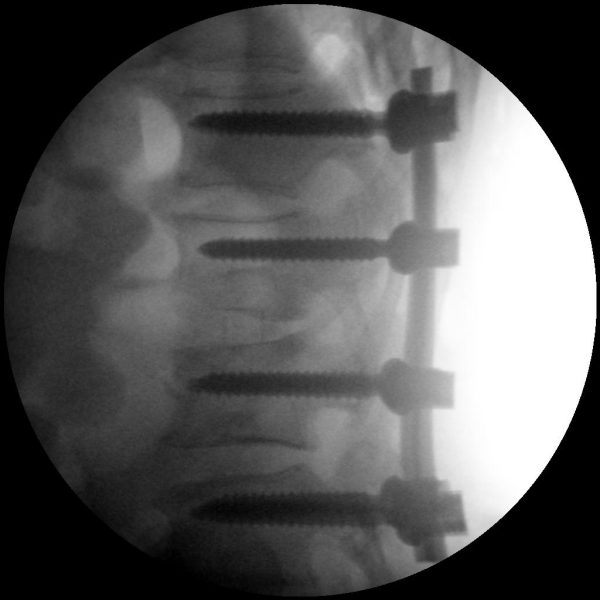

High-quality imaging

Skan-C uses advanced imaging technology, such as pulsed fluoroscopy and digital subtraction angiography, to provide highly detailed images of the affected area. This allows doctors to perform procedures with increased precision and accuracy, and better patient outcome

Clinical Evidence

Skan-C is a great C-arm for neurology treatments for several reasons